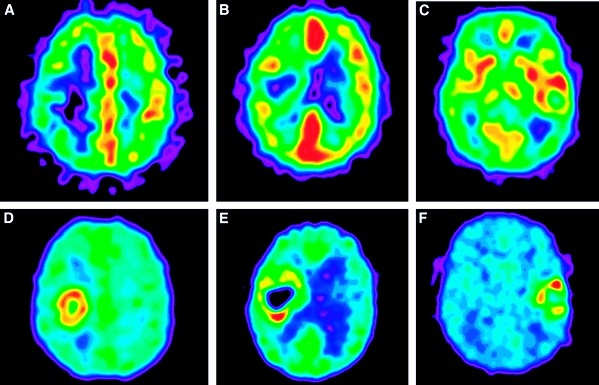

Диагностика

Выше уже было сказано, что симптоматика кислородного голодания мозга является вполне характерной, поэтому доктор уже после анализа симптомов и изучения анамнеза может поставить предварительный диагноз. Чтобы его подтвердить, человека могут отправить на дополнительные обследования: пульсоксиметрия, анализ газового состава крови в венах и артериях, изучение щелочно-кислотного равновесия. В отдельных случаях выполняется МРТ, КТ, УЗИ.

Полученных после этих обследований результатов хватит, чтобы со 100%-ной вероятностью диагностировать гипоксию. Чтобы выявить первопричину и основные характеристики заболевания, необходимо прохождение дополнительных обследований в соответствии с этиологией состояния человека.